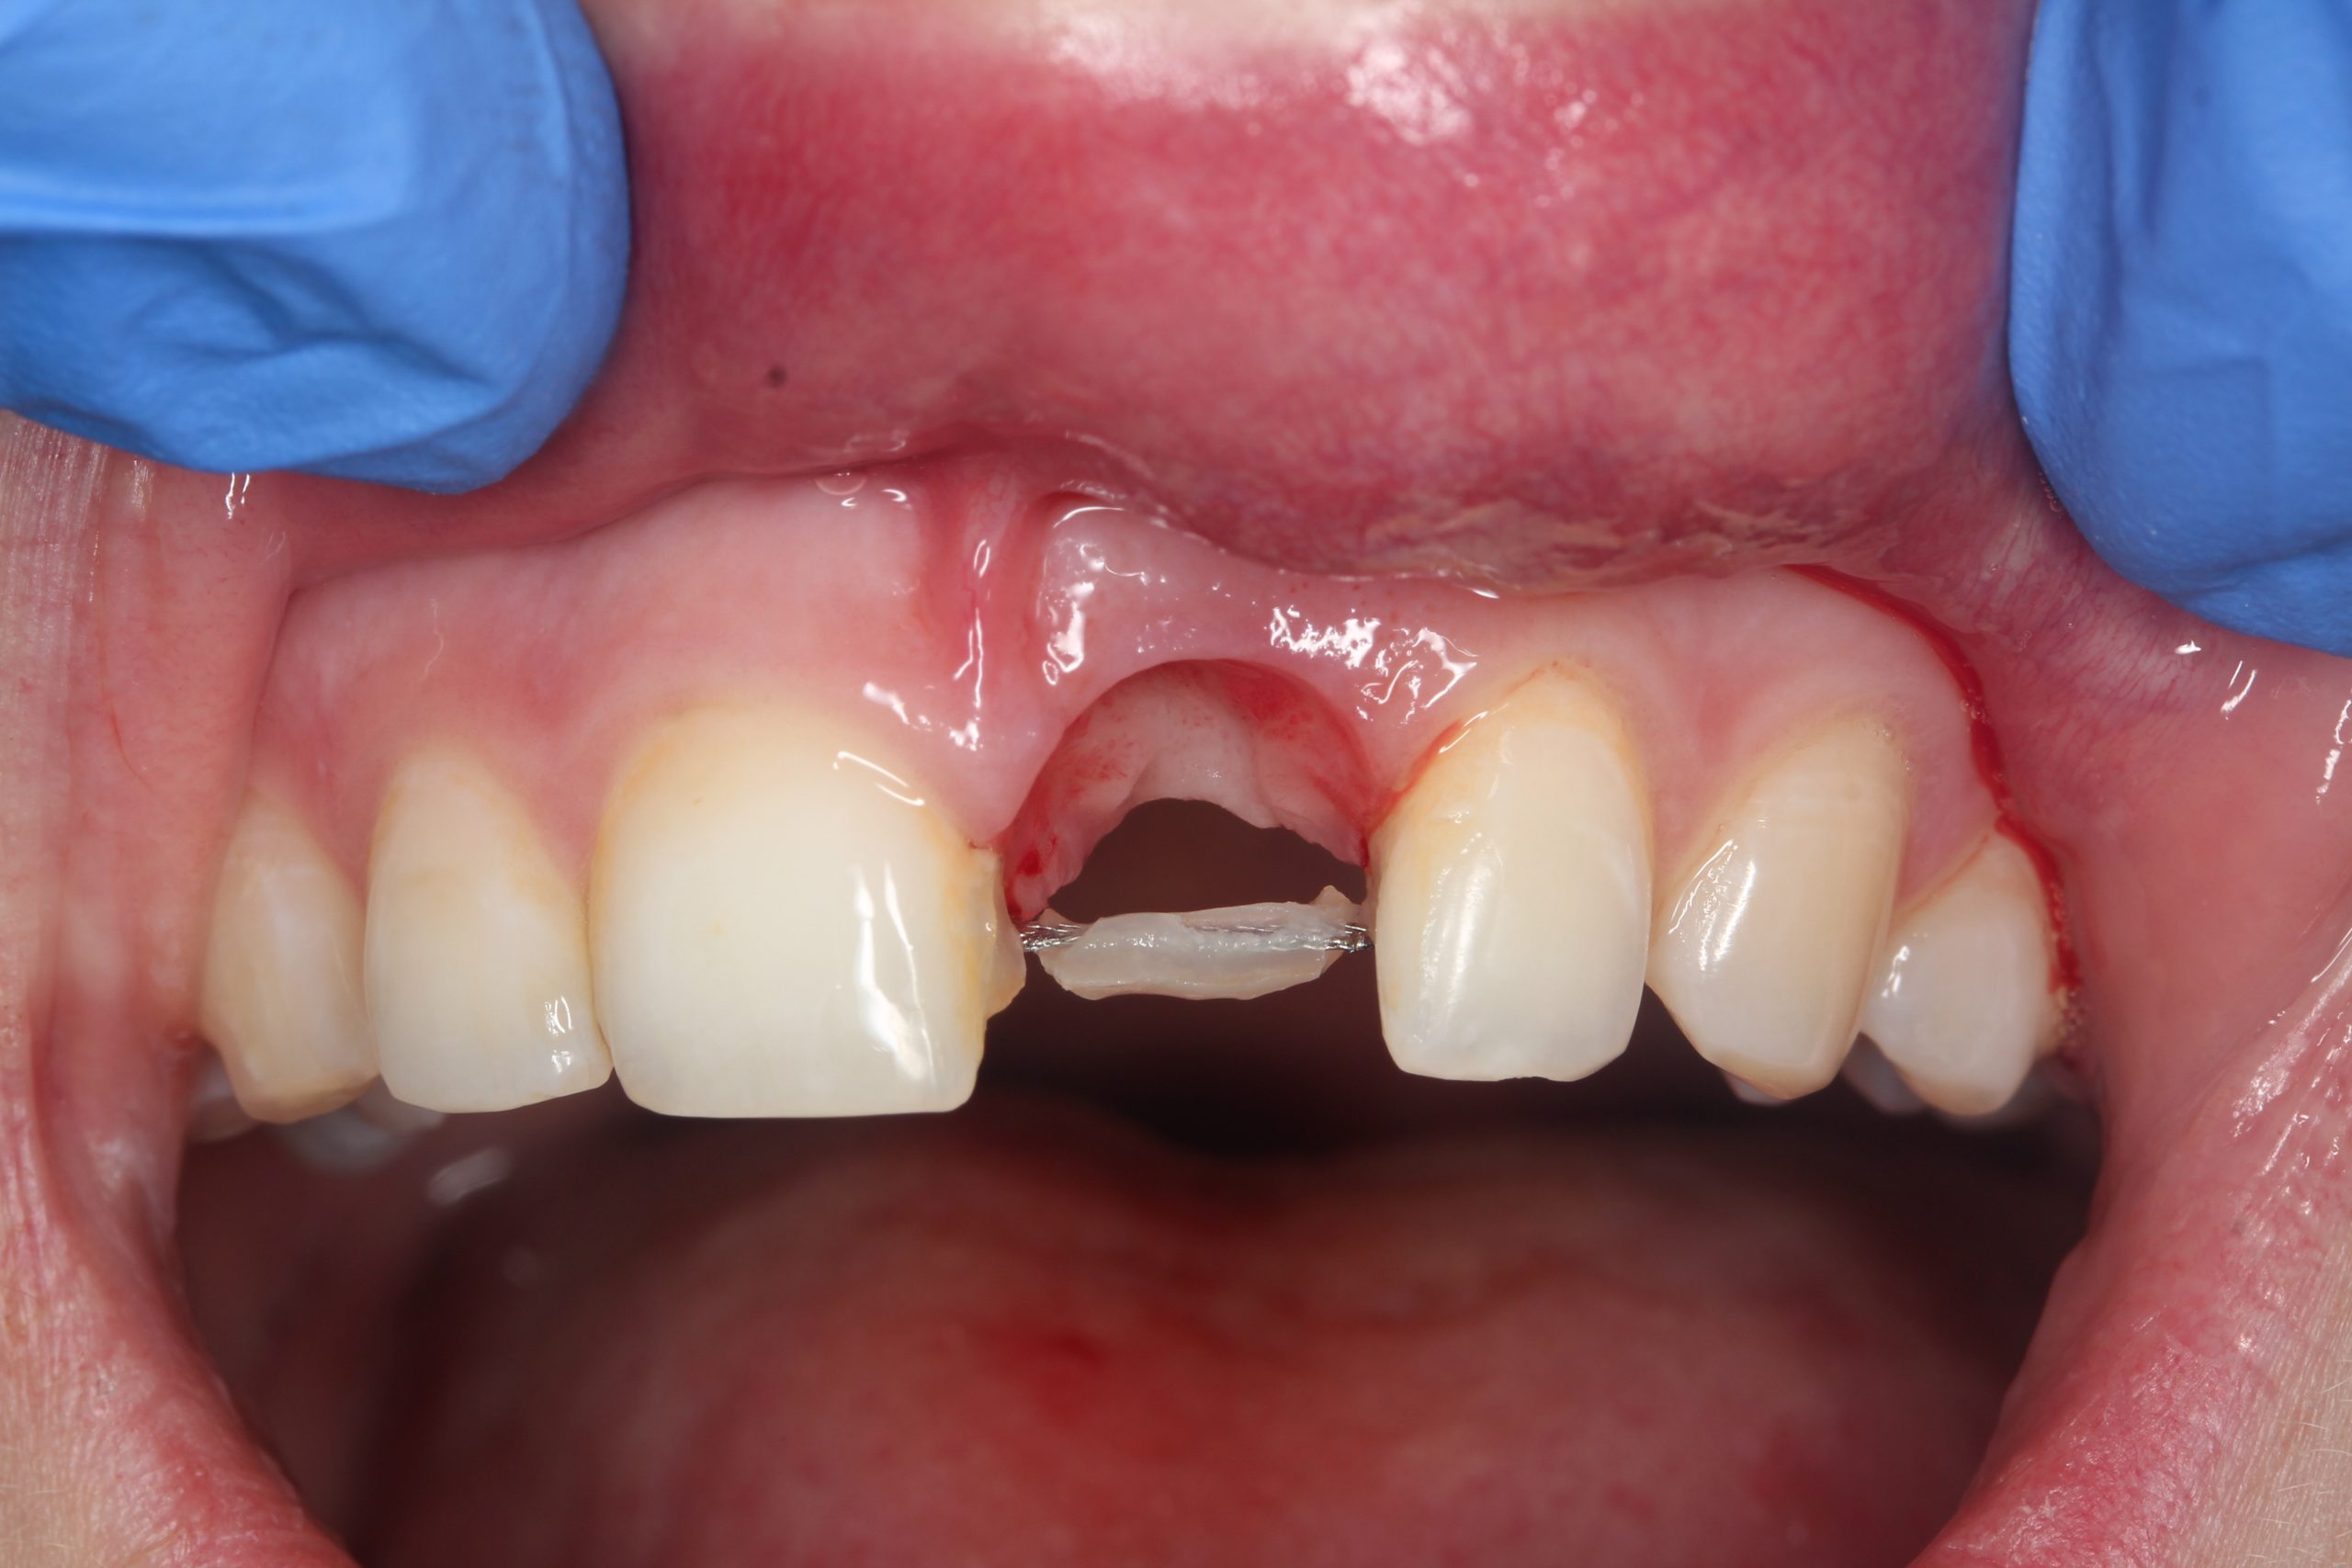

Nach der Extraktion und Exkochleation wurde die Extraktionswunde revidiert. Die vestibuläre Wand der Alveole war bis auf den apikalen Teil erhalten. Das Zahnbett wurde nur mit einem antibiotikahaltigen Kollagenkegel aufgefüllt.

Der extrahierte Zahn diente als Provisorium. Die Wurzel wurde etwa 2 mm unterhalb der SZG abgeschnitten, sodass dieser Teil im Weichgewebe eingebettet war. Die Krone wurde mit Komposit an den Nachbarzähnen befestigt.

Nach 14 Tagen überprüften wir die Einheilung und fixierten den Zahn erneut mit einem mehrsträngigen Draht von der Palatinalseite aus.